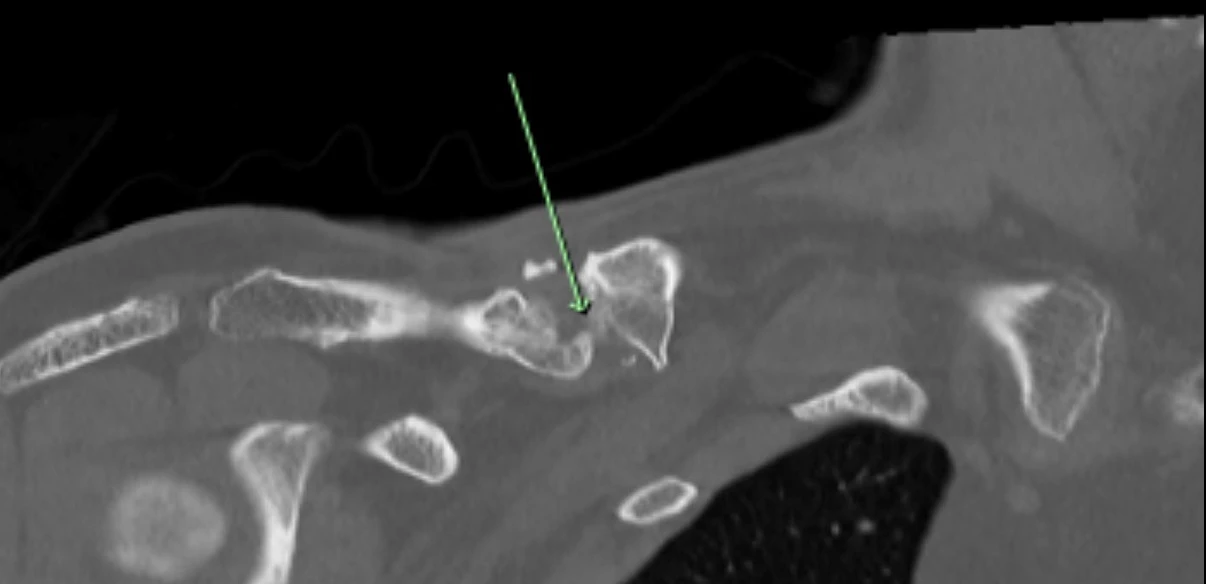

Subsequent imaging confirmed an established hypertrophic non-union of the right clavicle. CT scans and preoperative planning were arranged to assess the feasibility of surgical correction with bone grafting to restore clavicular length. A careful plan was put forward to possibly take down his nonunion, bone graft the defect and replate the clavicle.

This was all done with 3D CT imaging.

Pre op CT 1 showing site of non union

Pre op CT 2 showing site of non union

Pre op CT 2